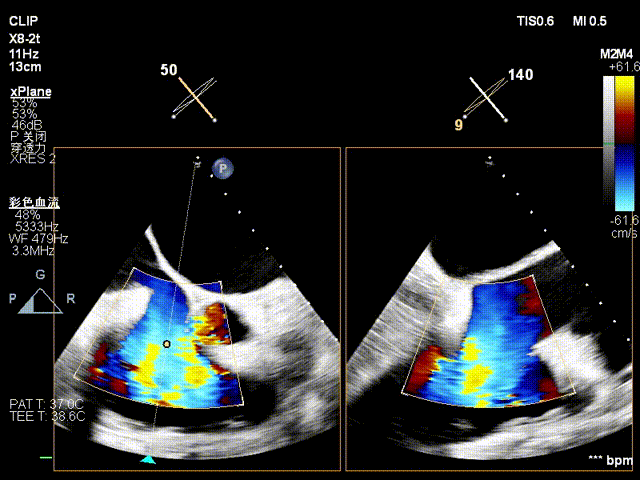

术前超声

术后超声